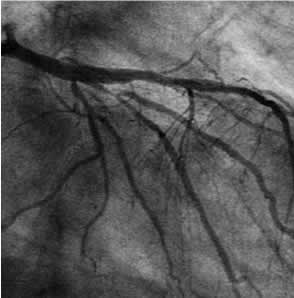

| Diagnosis: OMI (A), AP, TVD Present Illness: '01.9.28 Stenting for #3 (Multilink) |

| Final CAG Findings: '01.9.13 LVG: asynergy (A), EF: 39% CAG: #3 90% #5 75%, #6 ostial 100% #11 75%, #12 75% |

A-6 : 6 months follow-up angio